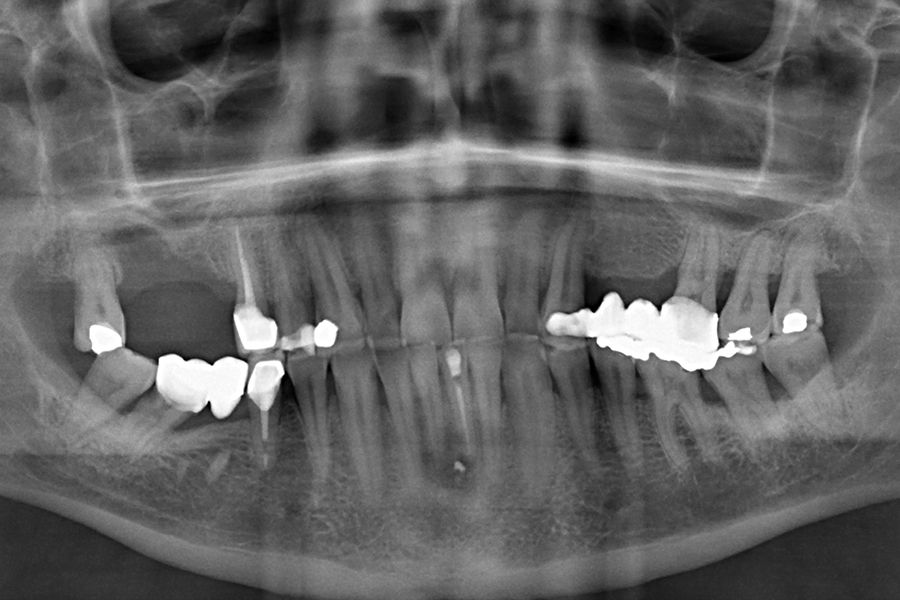

Material and method: We retrospectively recruited patients who attended our dental clinic with problems in different implant rehabilitations of an eminently mechanical nature (fracture of ceramics, prostheses, or components as well as implants) who underwent respiratory polygraphy to reveal the possible presence of OSA. In those cases where this disorder was found to be present, we selected patients with moderate-severe OSA (apnea- hypopnea index (AHI) ≥ 20) to analyze the different adverse events that occurred according to the severity of the sleep disorder recorded.

Results: Twenty-two patients who met the previously established inclusion criteria were recruited. Adverse events were identified in all patients in their implant restorations, these complications being fracture of the prosthesis ceramic (63.6%), structural fracture of the prosthesis in 18.2% of the cases (structure itself or resin coating in hybrids) and fractures or cracks in the implants in 18.2% of the cases. The mean AHI (apnea-hypopnea index) of all patients was 33.29 (+/- 18.90; range 20-110). If we analyze the presence of adverse events in the prostheses according to the AHI, we find that most adverse events are concentrated in the higher AHI ranges. A therapeutic approach with CPAP (continuous pressurized airway oxygen delivery device) combined with a mandibular advancement device (DIA) was used in two patients, the rest only DIA. With treatment completed, patients went from a mean AHI of 33.29 (+/- 18.90) to a mean of 17.38 (+-10.37), these differences being statistically significant (p<0.001).

sleep disorders such as OSA and oral pathology, for example bruxism or fractures, of various rehabilitations, both on teeth and on implants, is widely documented today. This association has been demonstrated in several epidemiological studies over the years3-7, with our research group highlighting that the presence of dental wear in patients should prompt a thorough sleep analysis, as the degree of dental wear is directly related to OSA via the AHI (apnoea-hypopnoea index)9-11. This relationship is directly proportional, and it is confirmed that patients with more severe wear also exhibit a higher AHI, which is likewise associated with an increased incidence of fractures in enamel, dental roots, and prostheses. Mechanical events may,

in some cases, also affect implants, resulting in bone defects due to overload, and in extreme cases, leading to fracture of the implant itself.12-14. In the following clinical case series, we sought to retrospectively collect a group of patients who experienced adverse events in implant-supported prostheses associated with mechanical overload (fractures, loosening), to whom a subsequent polygraphic sleep study was performed, identifying those in whom these events could be related to the presence of OSA. The most severe cases identified (AHI ≥ 20) were analysed to obtain data correlating both events (OSA and mechanical complications).